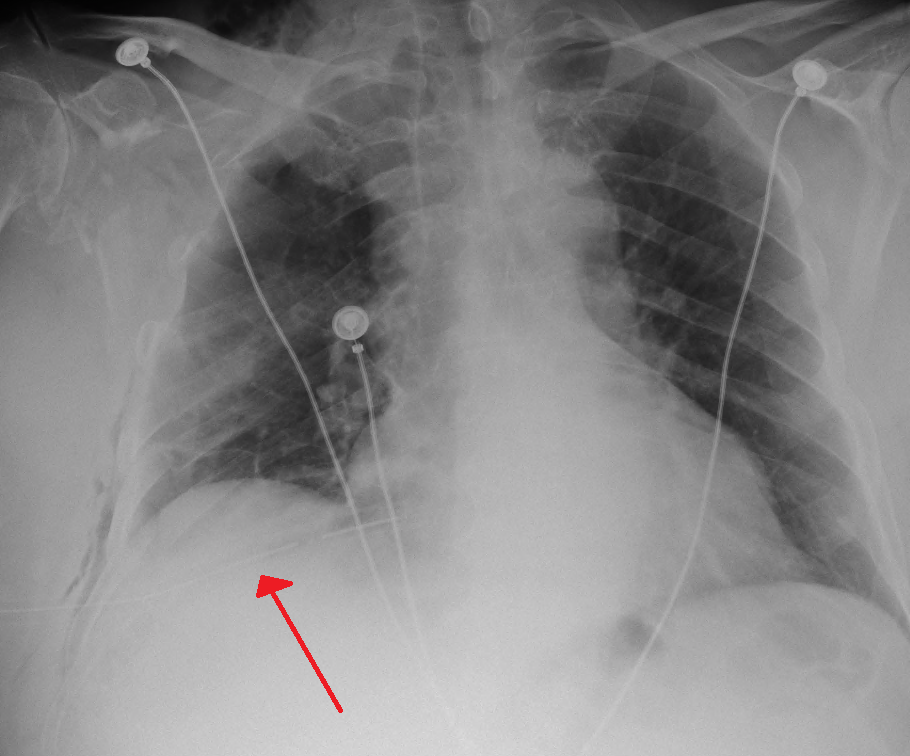

기흉으로 인하여 심장이 반대편으로 밀리면서 대정맥이 꺾이고, 정맥의 혈액이 심장으로 돌아오지 못하여 쇼크 상태가 되며, 한쪽 폐가 갑자기 기능부전에 빠지는 응급상황이다. 즉각 진단 및 치료하지 못하면 사망할 수 있다.[16] 이는 가슴 X-Ray 사진을 통해 파악할 수 있으며 긴장성 기흉 발생시 병원 응급실에서 병변이 있는 쪽의 2~3번 앞쪽 늑간에 굵은 주사바늘을 찌르고 흉관삽관술을 즉시 하여야 한다. 자연적 기흉(이를테면, 수포의 파열) 또한 폐의 손상된 부분을 밀봉하지 않아 누출되면 긴장성 기흉으로 악화될 수 있으니 주의해야 한다.긴장성 기흉은 일반적으로 기흉(원발성 자연 기흉, 속발성 자연 기흉 또는 외상성 기흉)이 호흡 및/또는 혈액 순환에 심각한 손상을 초래할 때 존재하는 것으로 간주된다.[16] 이는 폐쇄성 쇼크라고 하는 순환 쇼크의 한 유형을 유발한다. 긴장성 기흉은 환기, 소생술, 외상과 같은 임상 상황 또는 폐 질환이 있는 사람에게서 발생하기 쉽다.[15] 이는 응급 상황이며 추가 검사 없이 즉각적인 치료가 필요할 수 있다.[15][16]

흉부 방사선 사진 촬영으로 진단할 수 있다. 흉부 X선 검사에서 혈관 음영을 동반하지 않는 허탈된 영역은 기흉으로 의심된다.[72] 최대 흡기(숨을 참음) 중에 촬영한 일반 흉부 방사선 사진이 가장 적절한 첫 번째 검사이다.[30] 만기 중에 정기적으로 촬영하는 것은 이점이 없을 것으로 여겨지나,[31] 임상적 의심이 높지만 흡기 방사선 사진이 정상으로 보이는 경우 기흉을 감지하는 데 유용할 수 있다.[32]

기흉의 크기는 흉벽과 폐 사이의 거리를 측정하여 합리적인 정확도로 결정할 수 있다. 2cm의 공기 가장자리는 기흉이 반쪽 가슴의 약 50%를 차지한다는 것을 의미한다.[15]

기흉의 중증도는 다음과 같이 분류할 수 있다.[72]

| 경도 기흉 | 흉부 엑스레이 검사에서, 폐첨(폐의 꼭대기)이 쇄골보다 위에 있다. |

|---|---|

| 중등도 기흉 | 흉부 엑스레이 검사에서, 폐첨이 쇄골보다 아래에 있다. |

| 고도 기흉 | 흉부 엑스레이 검사에서, 폐의 허탈이 현저하다. |

| 긴장성 기흉 | 고도 기흉으로, 더욱이 폐에서 공기가 계속 누출되어, 흉강내가 양압이 되어 있다. |